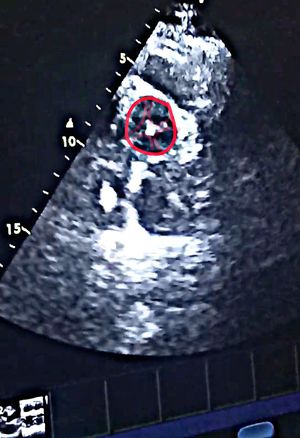

Quadricuspid aortic valve (QAV) is a rare congenital cardiac anomaly causing aortic regurgitation usually in the fifth to sixth decade of life. Earlier, the diagnosis was mostly during postmortem or intraoperative, but now with the advent of better imaging techniques such as transthoracic echocardiography, transesophageal echocardiography (TEE), and cardiac magnetic resonance imaging, more cases are being diagnosed in asymptomatic patients.